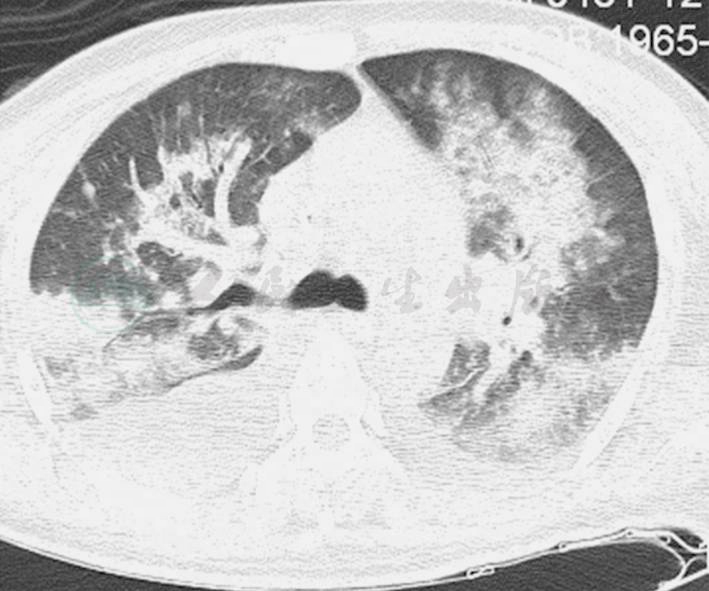

图2 起病第20天(入笔者医院第2天)CT提示两肺感染、渗出病变,双侧胸腔积液

5.胸部CT示双肺广泛感染、坏死、渗出病灶。

辅助检查:复查胸部X线、CT提示双肺广泛感染伴双侧胸腔积液(图1、图2)。